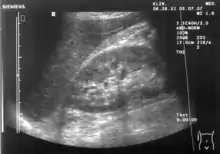

Ultrasound of liver (left side of the image) and right kidney (right side of the image) and Morison's pouch, not containing fluid